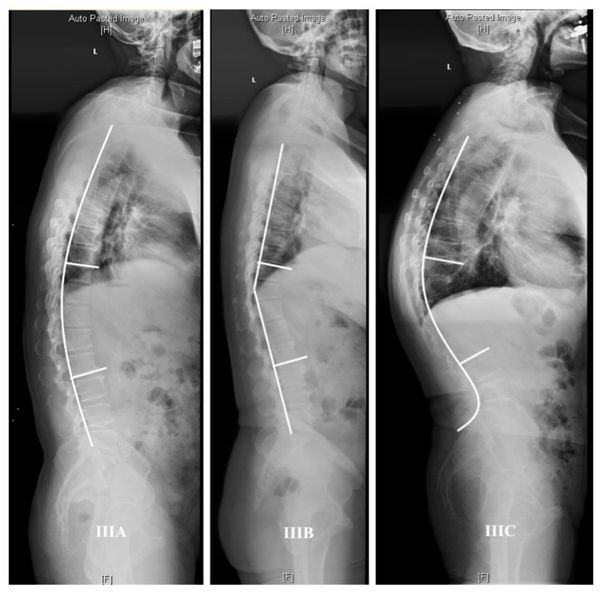

3. По степени тяжести (основана на измерениях угла по Коббу, проведённых по результатам рентгенографии):

- первая степень (угол искривления 30–40°) — сопровождается лёгкой сутулостью и усталостью;

- вторая степень (40–50°) — умеренная деформация, которая вызывает боль;

- третья степень (50–70°) — выраженная деформация, которая также сопровождается болевым синдромом;

- четвёртая степень (более 70°) — сильная деформация, при которой формируются тяжёлые осложнения [6].

Степени кифоза